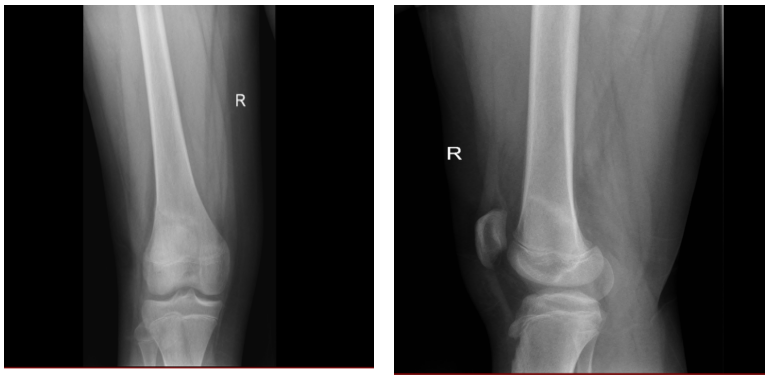

图1:男,14岁,蛙跳后右膝关节疼痛半月余。右膝关节正侧位X线平片显示股骨远端细带状骨质密度增高影。